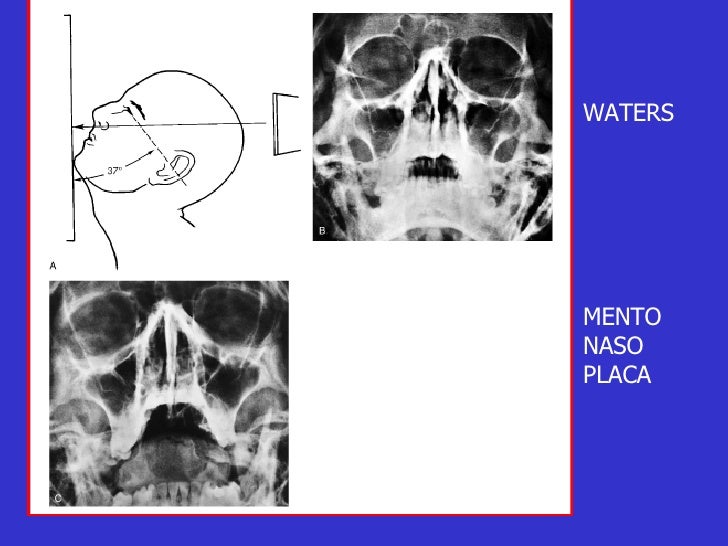

HUESOS PROPIOS DE LA NARIZ. PERFILOGRAMA (LATERAL) WATERS. ANTERO POSTERIOR (AP) PERFILOGRAFÍA (WATERS Y LATERAL) PERFILOGRAFÍA CON AP (WATERS, LATERAL Y AP) Para consultar precios y realizar cita, cóntactanos a los teléfonos. 55 58 19 15 59 y 55 20 75 47 97.

Radiología Tecnica de Waters - Descargar como PDF o ver en línea de forma gratuita. Proyeccion ap, lateral y oblicua del pie HillaryPerez7. Forma parte de serie radiográfica para evaluación de senos paranasales, junto a RX Caldwell y lateral de cráneo 4. La proyección de water es muy útil para estudiar el piso de la órbita,.

El estudio de "Rx Senos Paranasales 3 Proyecciones (Waters, Caldwell y Lateral)" implica la captura de imágenes radiográficas de los senos paranasales desde tres direcciones diferentes utilizando las técnicas de Waters, Caldwell y lateral. 1. **Técnica Waters**: En esta proyección, el paciente se coloca de pie o sentado con la cabeza.

grupos de senos. Proyección PA axial (Método Cadwell): Senos frontales y etmoidales anteriores. Proyección de Waters (Parietoacantial): con boca cerrada: Senos maxilares Proyección de Waters (Parietoacantial) con boca abierta: Senos maxilares y esfenoidales. Proyección Submentovertical: Senos etmoidal y esfenoidal. Centraje: Línea.